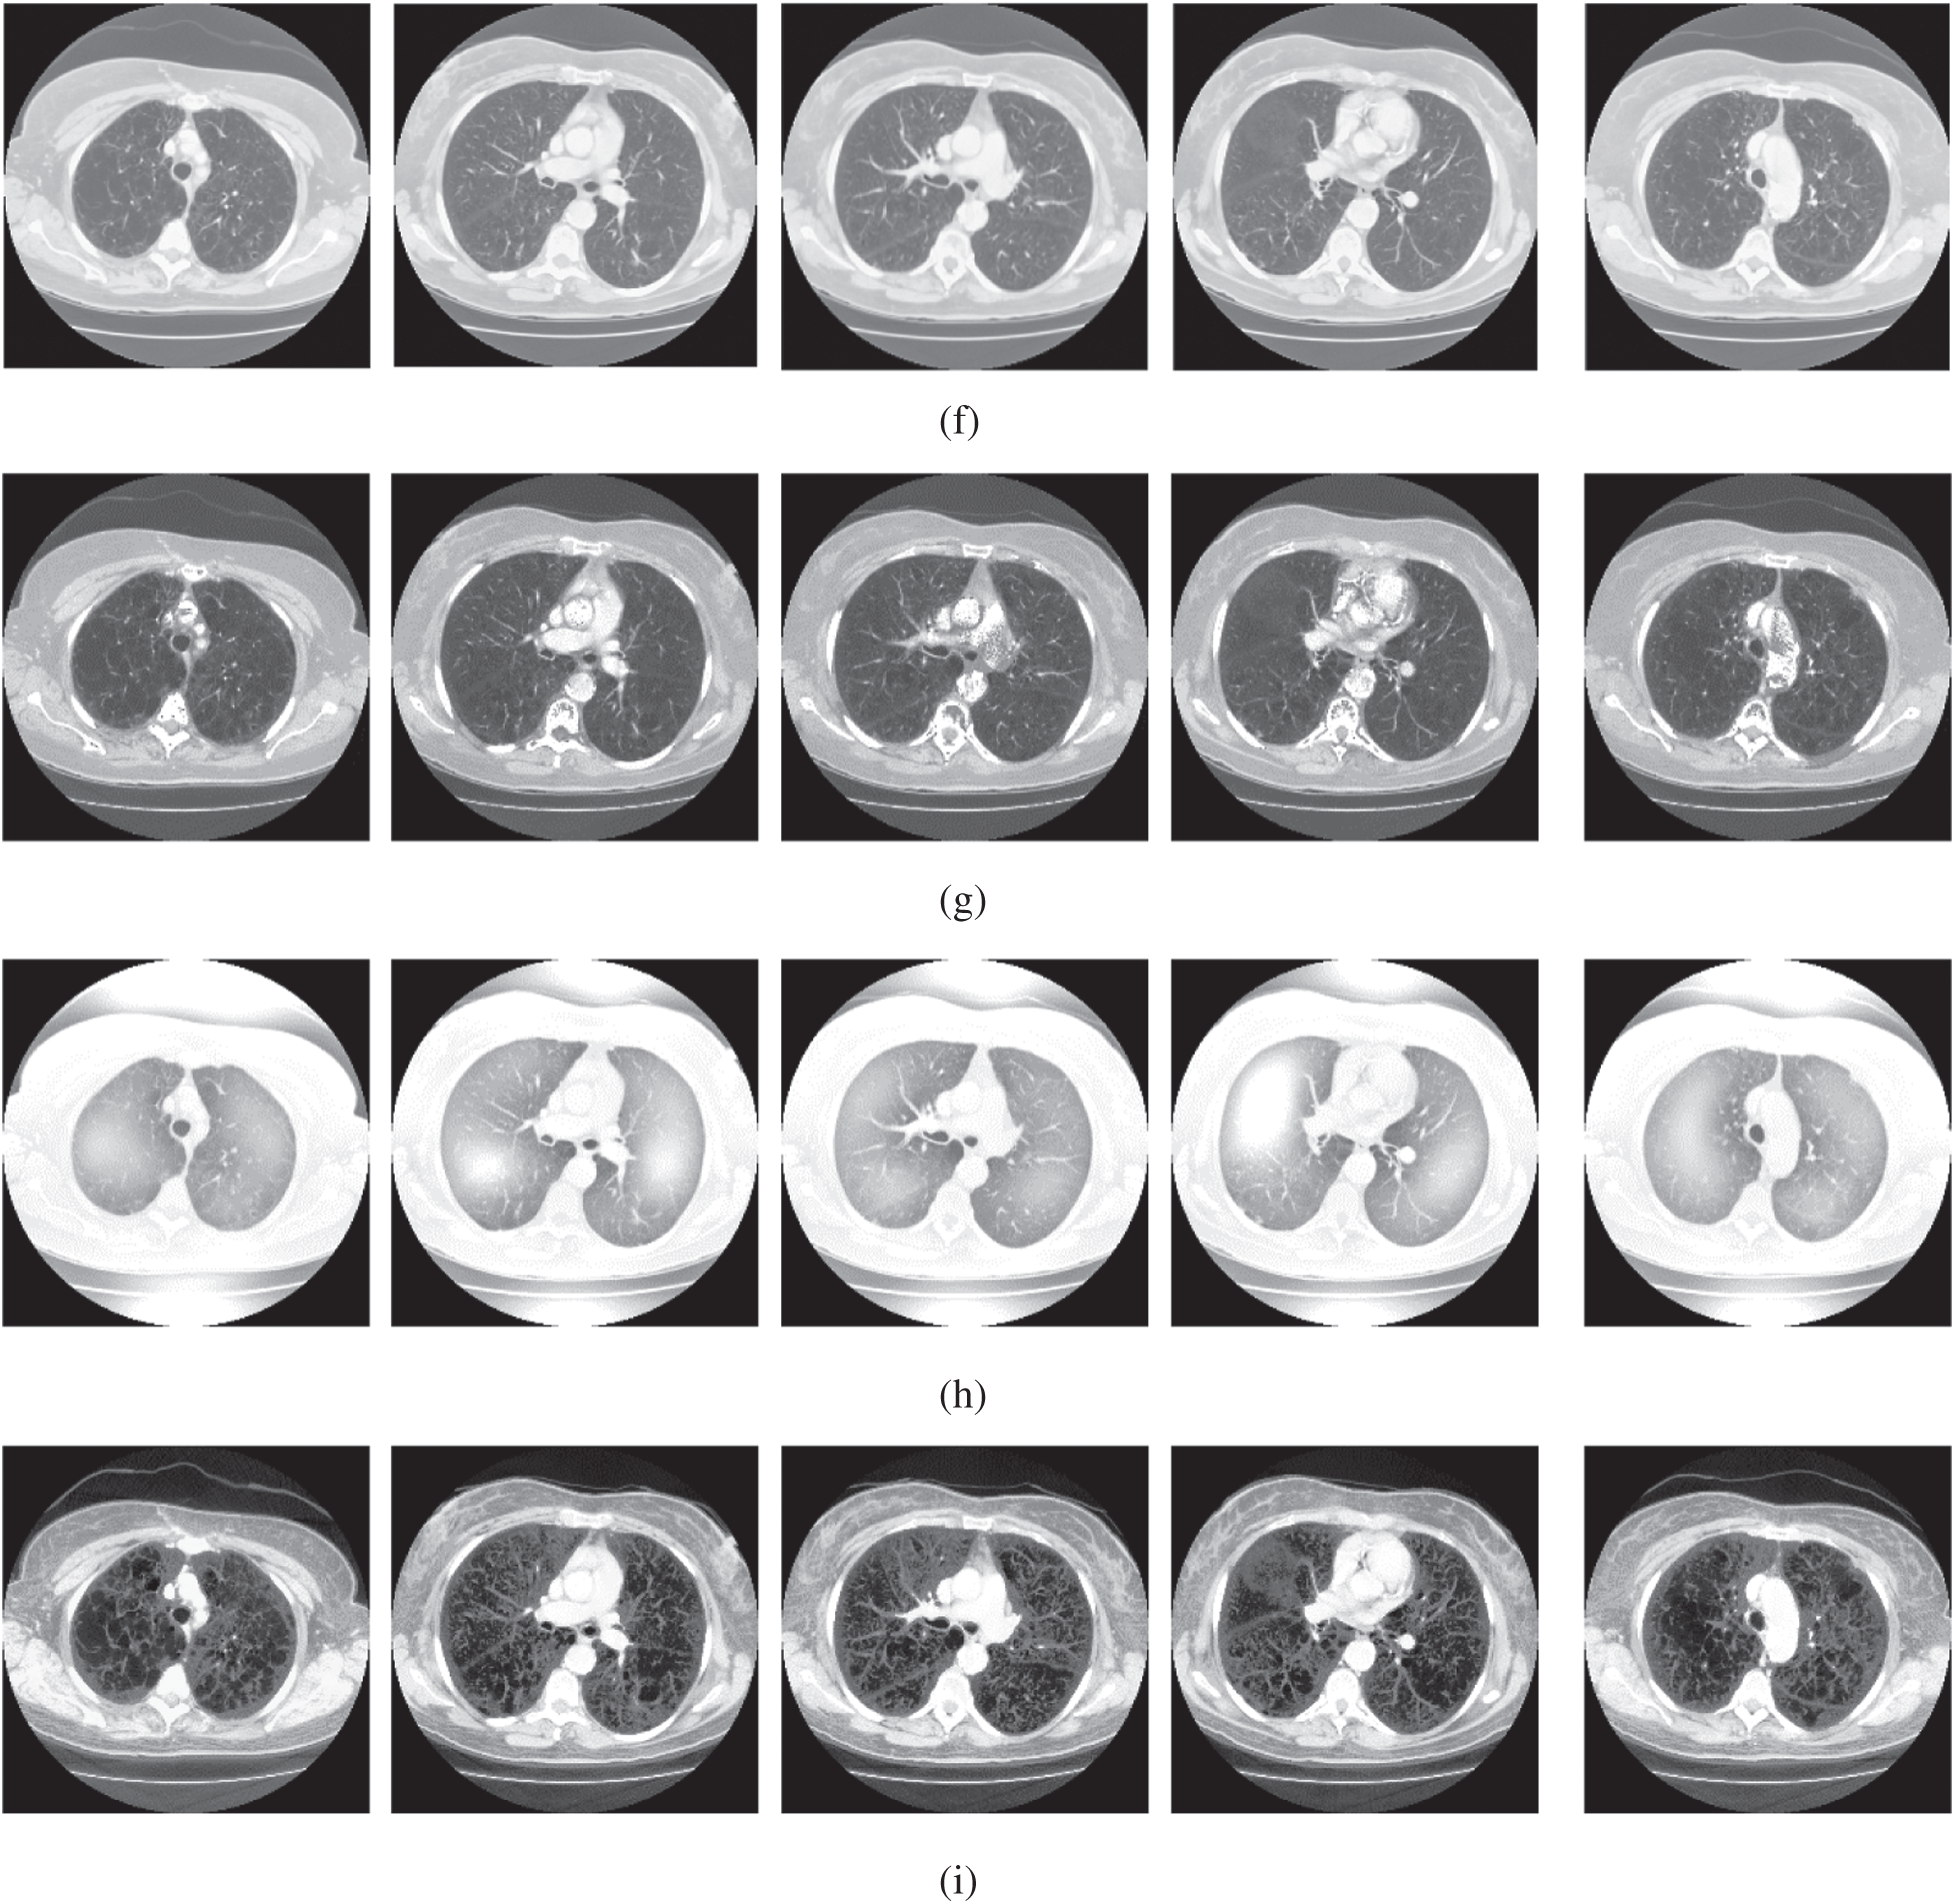

The qualitative results are illustrated in Fig. 3 for brain MRI; in Fig. 4 for lung CT, and in Fig. 5 for kidney MRI. As shown in the figures, all of the images have different trends with the dark and bright areas. It could be seen that the Histogram Equalization (b), Fu et al. [11] (f), and Zhang et al. [12] (h) methods produce over-enhanced images, while the proposed method produces natural appearance by enhancing the dark areas and maintaining the bright areas of input images. Overall, when we look at the input images and its enhanced images, the brightness of the fine details increases compared to the input images, irrespective of the content and application of the image. The brightening caused by the proposed FITE model makes the structures of the medical images well-defined and clear. The proposed FITE method introduces fair visual results for the weakly illuminated images. This is the contribution of fractional integral entropy in this study.

Figure 5: The kidney MRI enhancement results of the proposed and existing enhancement models. (a) Input image, (b) histogram equalization, (c) Al-Shamasneh et al. [4], (d) Raghunandan et al. [7], (e) Al-Ameen et al. [10], (f) Fu et al. [11], (g) Li et al. [17], (h) Zhang et al. [12], (i) proposed FITE